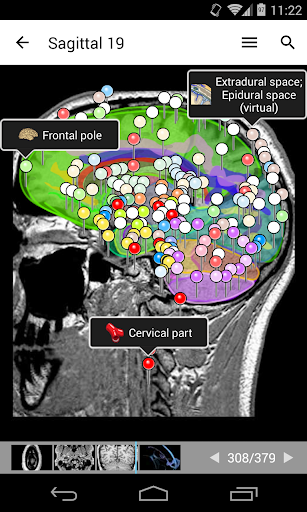

e-Anatomy memiliki lebih dari 26.000 gambar yang berisi serangkaian gambar dalam tampilan aksial, koronal, dan sagital serta radiografi, angiografi, gambar diseksi, bagan anatomi, dan ilustrasi. Semua gambar medis diberi label dengan cermat, lebih dari 967.000 label tersedia dalam 12 bahasa termasuk Terminologia Anatomica Latin.

- Gulir set gambar dengan menyeret jari Anda

- Perbesar dan perkecil

- Ketuk label untuk menampilkan struktur anatomi

- Pilih label anatomi berdasarkan kategori